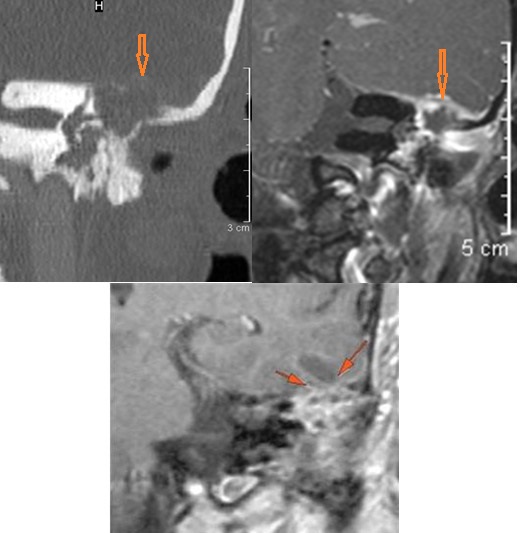

The basisphenoid and basiocciput (clivus) and/or the petrous apex inferior surface (mainly below the carotid canal) is eroded and/or its marrow space infiltrated. [Yes/No]

There is an erosive process, subperiosteal or otherwise spreading along the anterior-inferior aspect (extracranial aspect) of the petrous apex involving the bony Eustachian tube and/or carotid canal. [Yes/No]

The petrous apex is abnormal. [Yes/No]